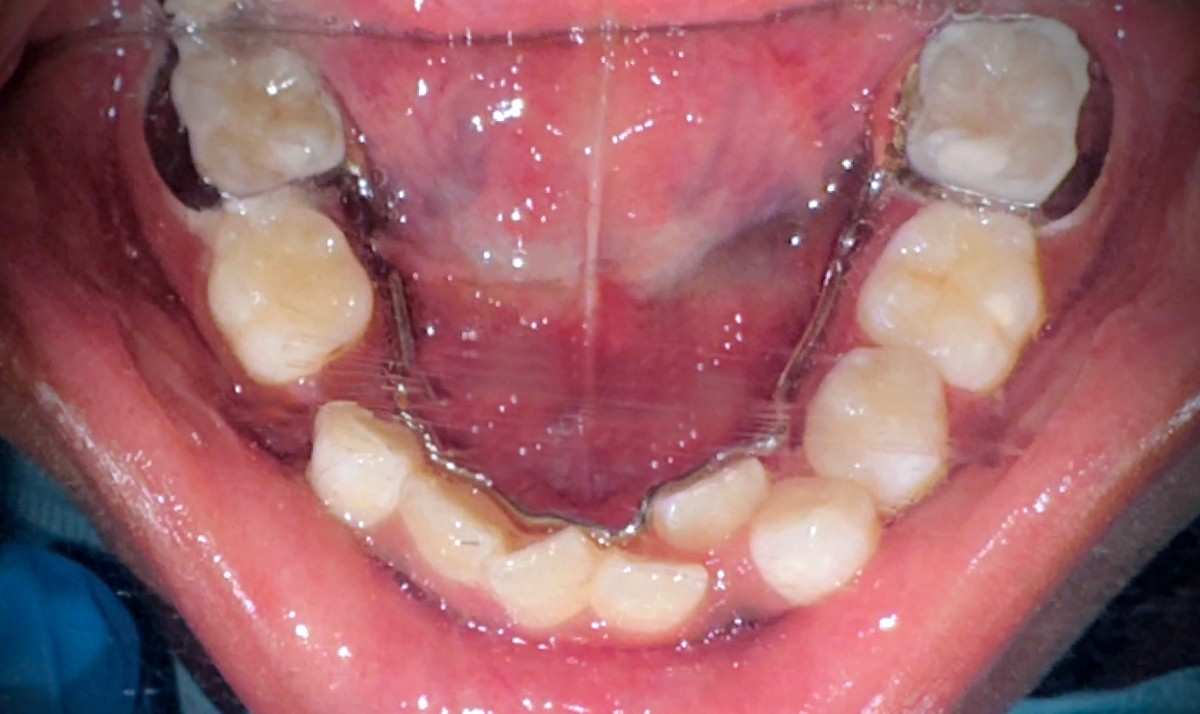

The diagnosis was accurate due to clinical and radiographic examination, & the lower primary molar is prematurely exfoliating. The clinical examination reveals that adjacent teeth have begun to fill the gap. An X-ray deprived of visible space and a 5-year loss potential revealed emerging permanent tooth buds in anticipated sites. Dr. Pooja was treated using a designed lingual holding arch with U-loops. The device helps to stabilize the molars to allow the adjustment to various mandible development. The parents were thoroughly informed about the process, benefits, and care needs were clarified.

The therapy was initiated by obtaining a dental impression with materials that do not cause discomfort to a child. It incorporated advanced 3D dental scanning technology, producing a perfect copy of the dental arch with perfect appliance fabrication.

The local anesthesia and isolation of U-loops through the rubber dam were optimal in providing ideal hygiene around the lower molars of the child, which Dr. Pooja cemented using a custom lingual holding arch.

Magnification tools were used to guarantee precise positioning. The U-loops were built into the arch to increase in size as the child develops. The whole process was effective and aimed at reducing the chair-time as much as possible and maximizing the comfort as much as possible.